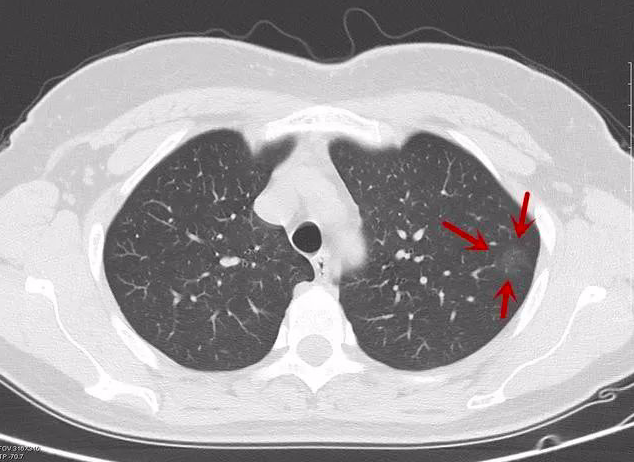

肺癌的ct影像图片

肺癌的ct影像图片,

大家帮忙看看这肺部ct片 能不能确定这就是肺癌啊 有什么保守疗法

正常肺对比肺癌ct图片

看不懂ct图像?各种类型肺癌典型表现!

中央型肺癌的ct表现

病例小细胞肺癌1例ct影像特征